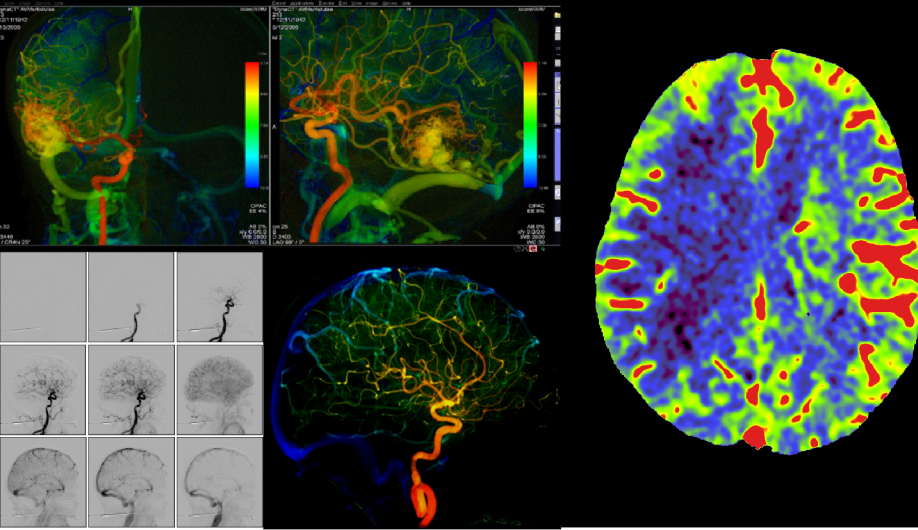

医院环境舒适,诊疗设备先进,拥有多间百级层流手术室和病房,国际领先的影像检查设备,如西门子128层螺旋CT、3.0T核磁共振、双平板心脑血管造影系统,同时配备多台国际先进的手术显微镜、神经内镜手术系统、术中导航定位系统、术中电生理监测系统,以及高级神经外科复合手术室,为患者脑脊髓脊柱疾病的筛查、保健、手术和微创治疗,提供精准、有效、微创和安全的保障。

西门子双C臂血管造影系统